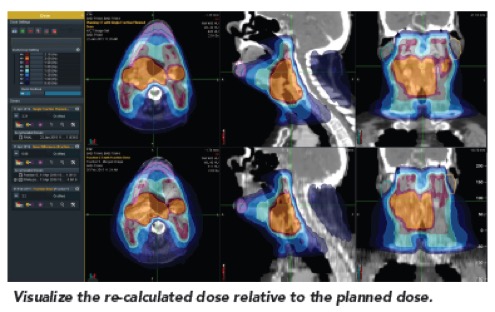

II. Αυτόματη παρακολούθηση της χορηγούμενης ακτινοθεραπευτικής αγωγής

Το σύστημα περιλαμβάνει εργαλεία που επιτρέπουν στον ακτινοθεραπευτή ιατρό να παρακολουθεί την εκτέλεση της ακτινοθεραπείας και να ενημερώνεται αυτόματα για τις περιπτώσεις εκείνες που απαιτείται αναπροσαρμογή του πλάνου θεραπείας.

Το σύστημα περιλαμβάνει εργαλεία που επιτρέπουν στον ακτινοθεραπευτή ιατρό να παρακολουθεί την εκτέλεση της ακτινοθεραπείας και να ενημερώνεται αυτόματα για τις περιπτώσεις εκείνες που απαιτείται αναπροσαρμογή του πλάνου θεραπείας.

- Σύντηξη των παραμέτρων του πλάνου θεραπείας (π.χ., περιγράμματα στόχου και κρίσιμων οργάνων) με τις καθημερινές εικόνες αξονικής τομογραφίας λαμβάνοντας υπόψη τις ανατομικές και βιολογικές μεταβολές του ασθενούς

- Υπολογισμός της καθημερινά χορηγούμενης κατανομής δόσης

- Υπολογισμός της αθροιστικά χορηγούμενης δόσης